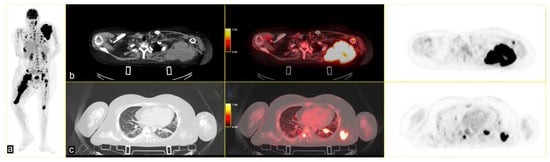

Following instrumental and clinical disease progression, the patient was treated with Sirolimus (an m-TOR inhibitor). At the first re-evaluation, instrumental progressive disease (PD) was observed with a moderate increase in bone SUVmax, particularly in the left scapula (SUVmax 34.8 vs. 31), and by the appearance of new lesions, such as the right iliac wing, numerous pulmonary nodules (SUV max 6) and lymph nodes in the left axilla (SUVmax 6.1) [Figure 3].

Figure 3.

PET/CT fused images show large hypermetabolic lesions in (a) the right femur, (b) the left scapula (with erosion of the cortical part), (c) thickened osteogenic lesions in the pelvis and bilateral iliac wings (thickened osteogenic lesions in with lower SUVmax: 6.7). From left to right CT PET/CT fused images and PET images.